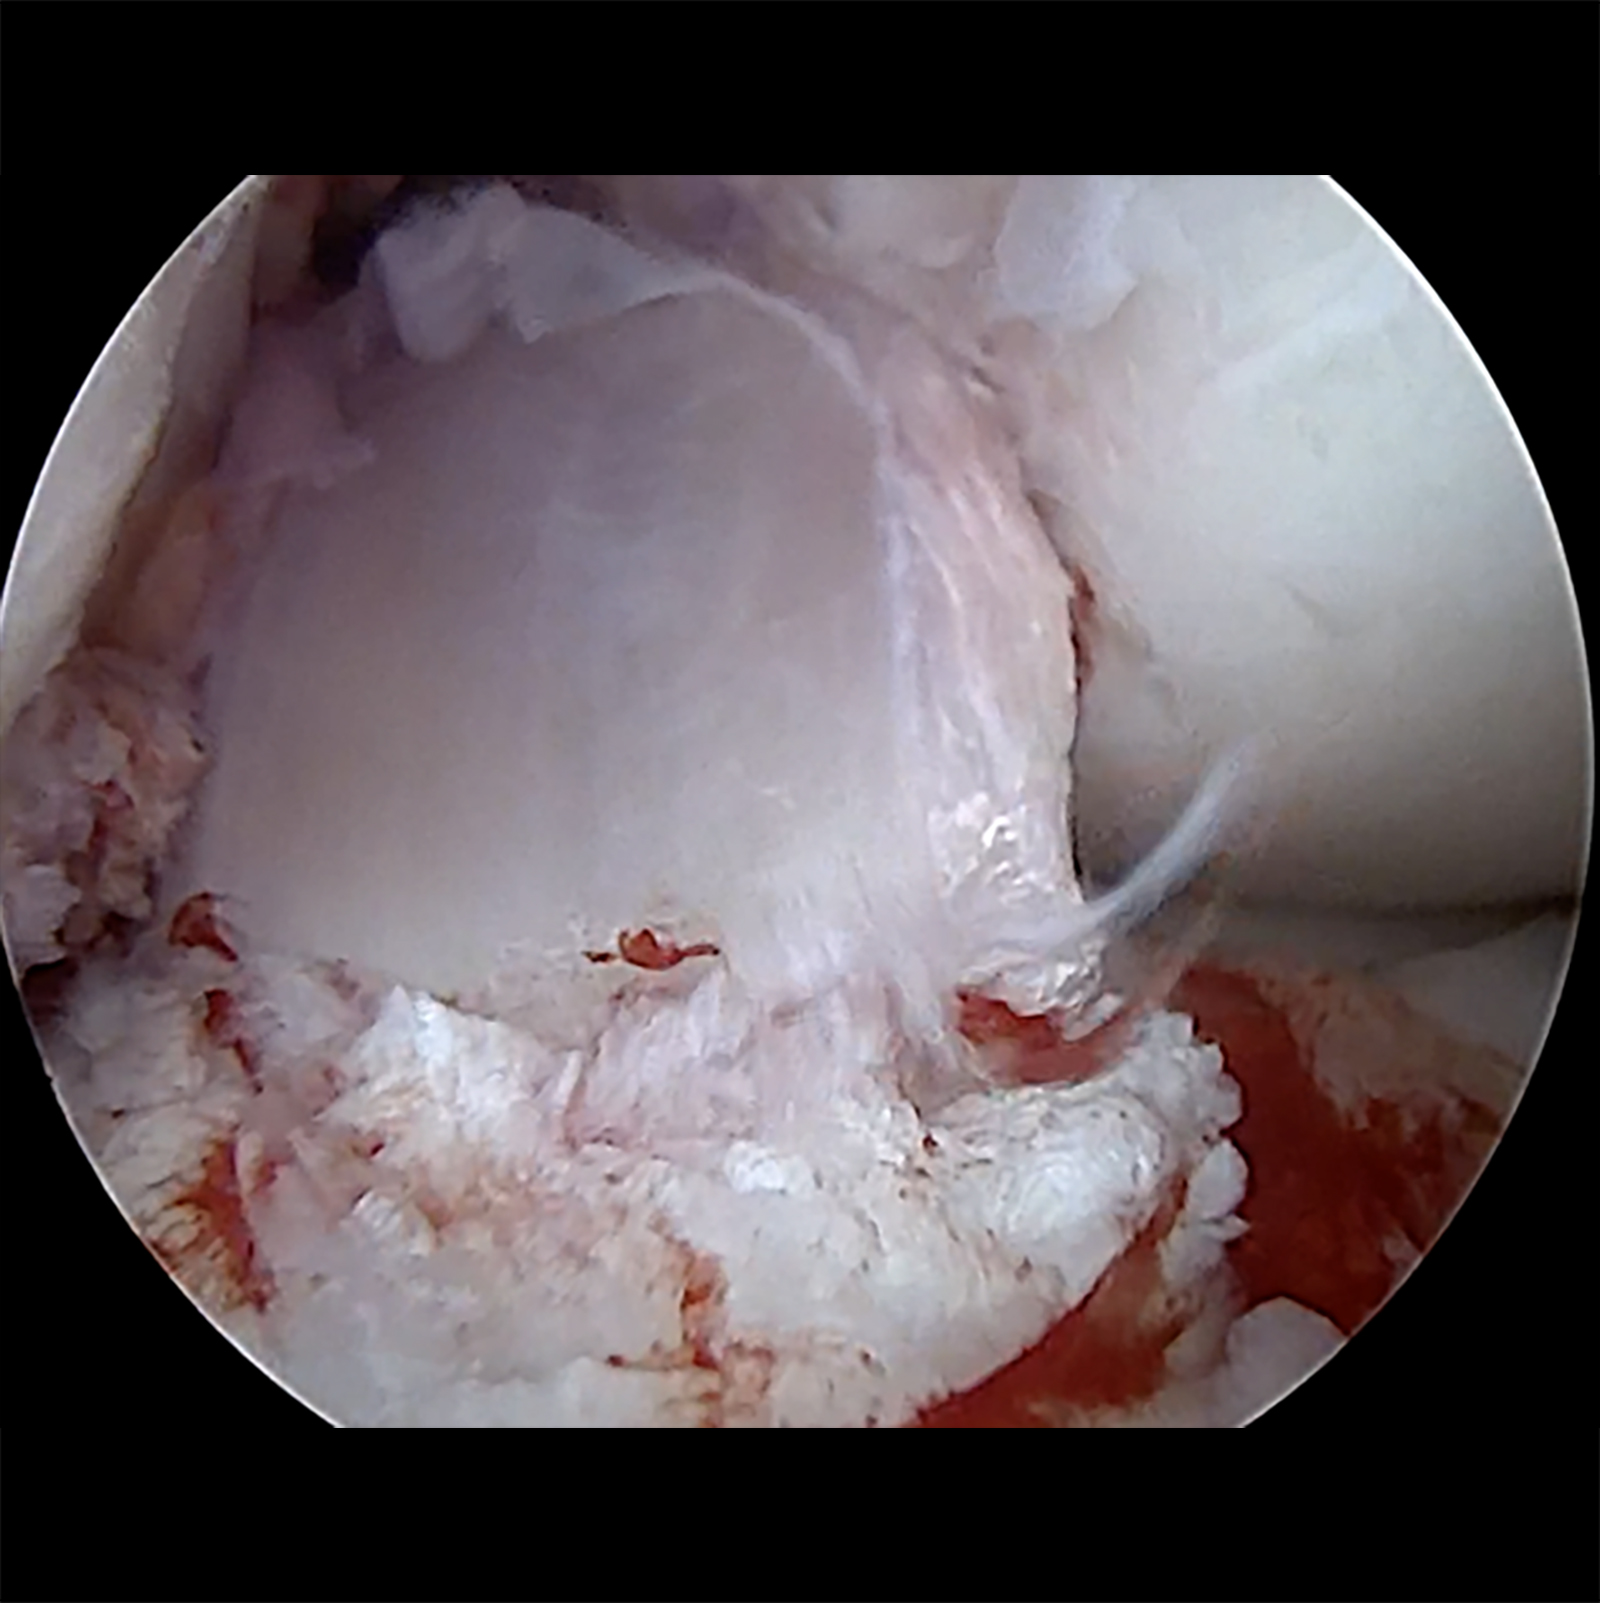

Die anatomische Bohrkanalpositionierung mit adäquatem Graftdurchmesser Durchmesser (in Abhängigkeit von der Notchgröße: ♀> 8 mm; ♂︎ > 8,5 mm) und die Adressierung der peripheren Stabilität sind die „Must Haves“ der modernen Kreuzbandchirurgie [18]. Unter Belassen der originären Kreuzbandfasern ermöglicht der ACL „remnant“-preserving Technique die Implantation des Grafts in die alten Fasern in der anatomischen Positionierung. Aktuelle Reviewanalysen zeigen hierüber die schnellere Einheilung des Grafts („Maturation“) und sekundär geringere Reinstabilitätsraten bei vergleichbarer Komplikationsrate gegenüber der Standard-Kreuzbandoperation [13, 18 – 22].

Primär zu differenzieren ist die anterolaterale und die anteromediale Kniegelenksstabilität (ALRI und AMRI), die Kombination ist mit Ausnahme von Multiligamentverletzungen eher selten. Die kombinierte anatomische Rekonstruktion des vorderen Kreuzbandes, der anterolateralen Kapsel-Band-Rekonstruktion (ALL-Plastik, Rekonstruktion nach Lemaire, Müller, Ellison, o. ä) und bei entsprechender Instabilität des posteromedialen Meniskus-Band-Komplexes stellen den derzeitigen Goldstandard dar, wobei kein wissenschaftlich klinischer Unterschied in den o. g. anterolateralen Rekonstruktionstechniken derzeit besteht. Eine vermehrte Belastung des lateralen Kompartimentes durch das additive Verfahren besteht nicht [24]. Die additive periphere Stabilisierung zur Vorderen Kreuzbandrekonstruktion führt zu einer signifikant geringeren VKB-Reinsuffizienz (von 10 – 15 % auf unter 5 %) und verbesserten Meniskuskonsolidierung, sodass in Zusammenschau mit der aktuellen Literatur zunehmend von einem „Must have“ der modernen Kreuzbandchirirgie gesprochen werden sollte [10 – 13]. Bei Vorliegen einer kombinierten anteromedialen Kniegelenksinstabilität ist die anteromediale Bandrekonstruktion additiv zur vorderen Kreuzbandrekonstruktion alternativlos, da die verbleibende AMRI obligat zu einem (zumeist atraumtischen frühen) Versagen der Kreuzbandplastik führt.